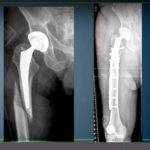

Periprosthetic fractures after Total Hip Replacement

Courtesy: Yasser Khatib, Penrith NSW 2750, Australia